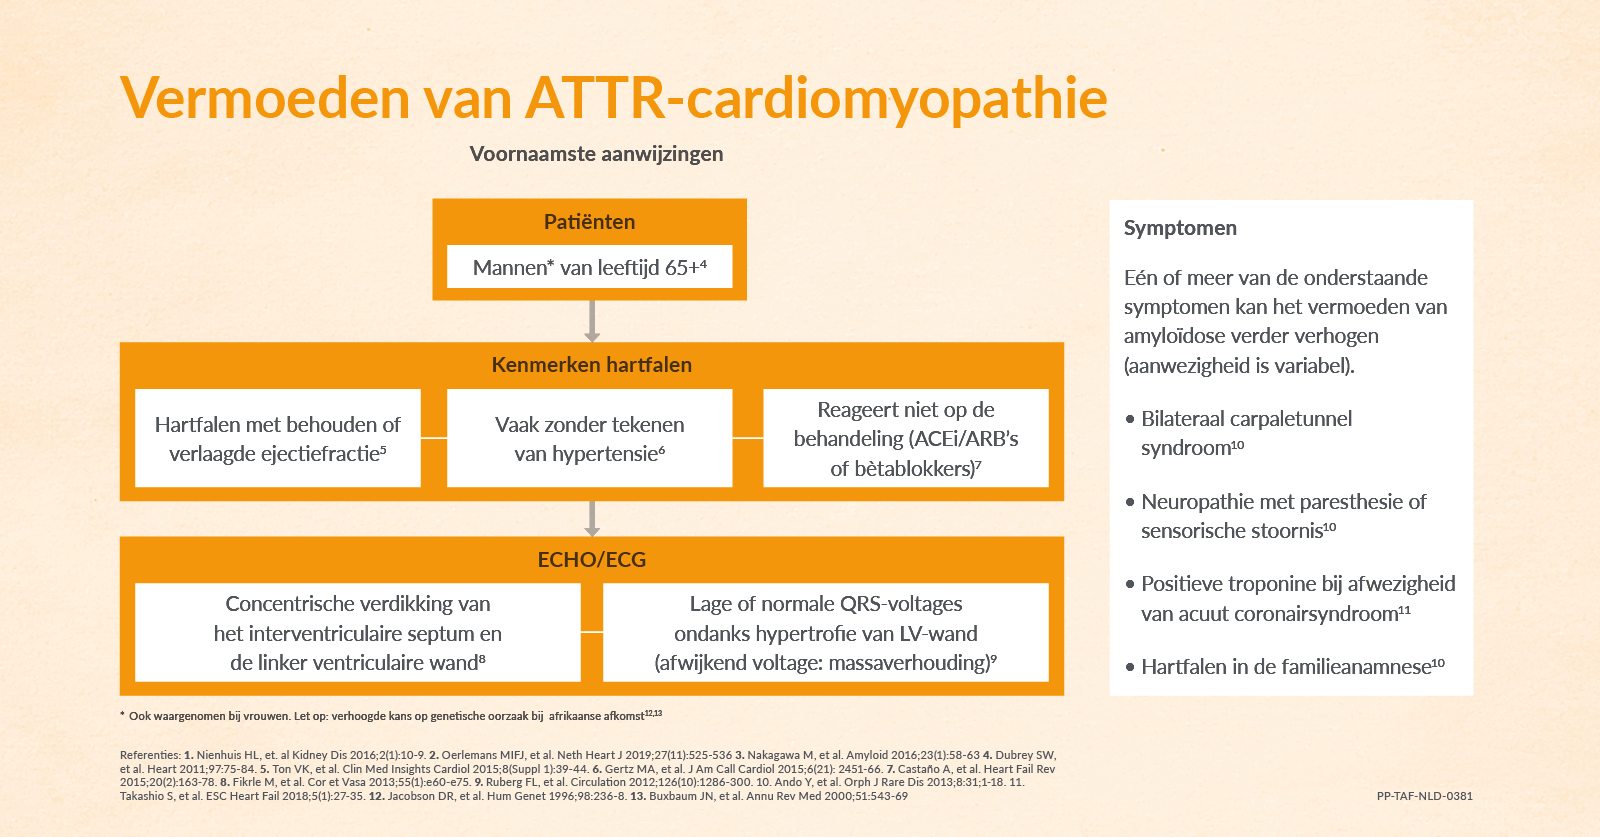

Bent u op zoek naar de oorzaak van hartfalen bij uw patiënt? Of heeft u het vermoeden dat er sprake is van ATTRwt als onderliggend lijden? Bekijk onderstaand schema met de belangrijkste aanwijzingen die in verband zijn gebracht met deze aandoening.

Beschrijving tonenEen bekend ECG-kenmerk van ATTRwt is een laag of normaal QRS-voltage, ondanks hypertrofie van het linkerventrikel.8

Hoe is dit te verklaren? Een verdikte wand is het gevolg van zich opstapelende amyloïdfibrillen, en niet van vergrootte hartspiercellen.8

Let op, bij cardiale amyloïdose is niet altijd sprake van de ‘klassieke’ lage QRS-voltages. Bij cardiale amyloïdose zien we een discrepantie tussen de toegenomen dikte van het myocard op een echo en de omvang van de voltages op het ECG. Het is daarom van belang om niet alleen naar lage voltages te zoeken. Waarom? Dit ECG-kenmerk is pas in een laat stadium van de ziekte waar te nemen. En dat maakt het wellicht minder nuttig om cardiale betrokkenheid snel te diagnosticeren.9

Figuur 1: Voorbeeld van ECG afbeelding die de QRS-spanning van extremiteitsafleidingen weergeeft bij een patiënt met cardiale amyloïdose en verdikte LV wand. -